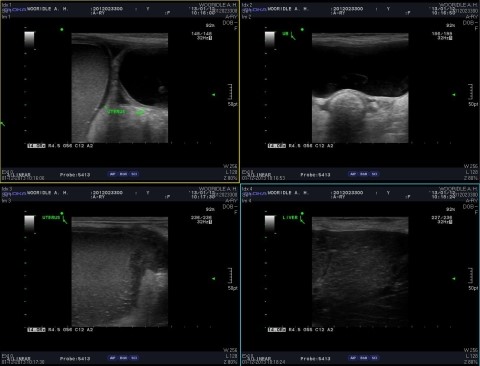

심장과 폐, 신장 등 흉복부 주요 장기의 이상 문제를 확인하기 위한 방사선 검사와 함께 초음파 검사를 실시했습니다.

복부 초음파 검사상

담낭 내에 담석이 발견되어 양쪽에 뚜렷한 낭포성 자궁내막 증식, 액체저류, 자궁수의 뚜렷한 비후를 보고 자궁축농증을 의심/진단할 수 있었습니다.

더불어 오른쪽 난소와 자궁 위치에서 종양이 의심되는 종괴를 확인할 수 있었습니다. 그 외 추가 질환 존재 여부를 확인하기 위해 CT 촬영을 결정했습니다.